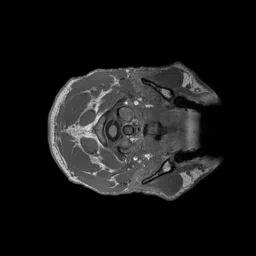

The most important kind of structural MR image is called a T1-weighted image. Precisely what T1-weighted images measure is beyond the scope of this document, but T1-weighted images are useful for imaging the brain because voxels tend to be bright when the concentration of fat is high and low when the concentration of water in the voxel is high. When a T1-weighted image is taken of the brain, the brain appears much brighter than the cerebrospinal fluid around it, making the voxels that are part of the brain easy to distinguish from the voxels that are not (Fig. 5). Additionally, the white matter voxels appear brighter than the gray matter voxels because white matter contains myelin, which has high fat content. Because of these contrasts, T1-weighted images are useful for determining the precise shape of the brain and in particular the white and gray matter, which have complex folded shapes.

Figure 5. A T1-weighted image, rendered one slice at a time. The anatomical structures in the head and neck as well as the shape of the white and gray matter of the cerebral cortex are clear due to the contrast differences in the tissues.#